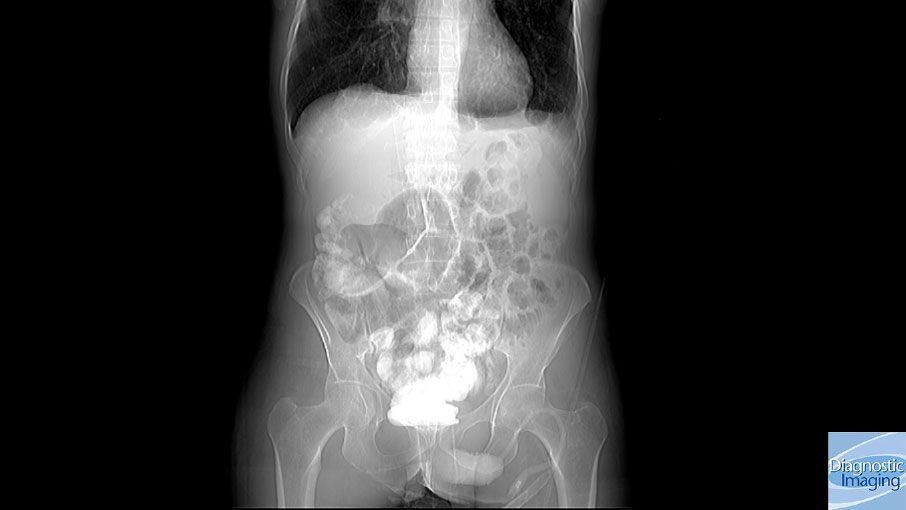

Case History: 45-year-old patient presented with complaints of vomiting for a few days.